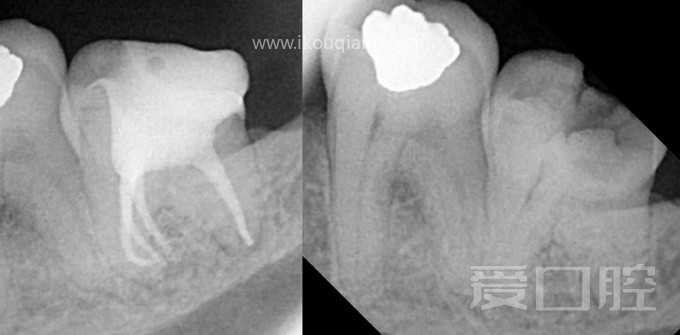

看个根充 —— 下8